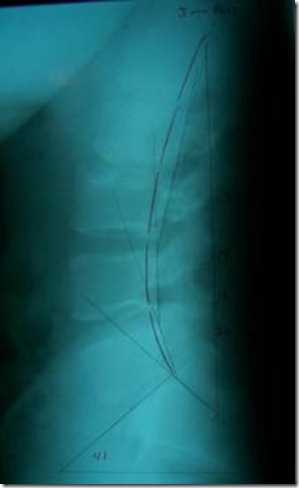

After 15 treatments, this patient was re-evaluated. He had a complete resolution of his pain and no impairment of his normal lumbar range of motion. His post-treatment lateral lumbar x-ray revealed an improved upper lumbar lordosis, a normal 41 degree sacral tilt and a reduction of his posterior thoracic translation to just three millimeters (See x-ray #2).

Figures: X-ray #1 and #2